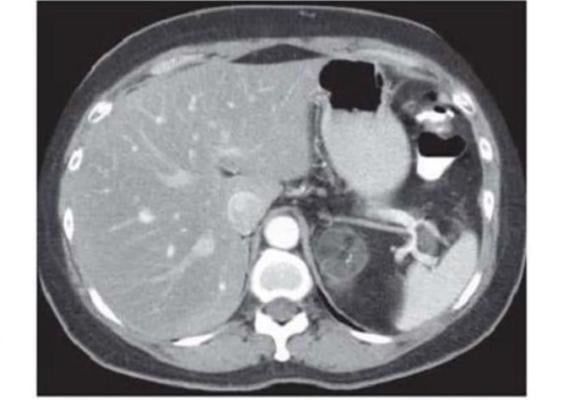

Sept. 3, 2024 — Researchers evaluating the performance of ChatGPT-4 Vision found that the model performed well on text-based radiology exam questions but struggled to answer image-related questions accurately. The study’s results were published in Radiology, a journal of the Radiological Society of North America (RSNA).

GPT-4 Vision answered 246 of the 377 questions correctly, achieving an overall score of 65.3%. The model correctly answered 81.5% (159) of the 195 text-only queries and 47.8% (87) of the 182 questions with images.

The model performed best on image-based questions in the chest and genitourinary subspecialties, correctly answering 69% and 67% of the image-containing questions, respectively. The model performed lowest on image-containing questions in the nuclear medicine domain, correctly answering only 2 of 10 questions.

“Our study showed evidence of hallucinatory responses when interpreting image findings,” Dr. Klochko said. “We noted an alarming tendency for the model to provide correct diagnoses based on incorrect image interpretations, which could have significant clinical implications.”

“Given the current challenges in accurately interpreting key radiologic images and the tendency for hallucinatory responses, the applicability of GPT-4 Vision in information-critical fields such as radiology is limited in its current state,” he said.